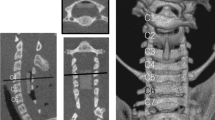

Spinal cord edema contributes to the pathophysiological mechanisms underlying spinal cord injury (SCI) and is associated with functional recovery after SCI. Early myelotomy may be a promising surgical intervention for reducing SCI-induced edema. However, it remains unclear whether myelotomy can reduce SCI-induced edema. In addition, aquaporin-4 (AQP4) and aquaporin-9 (AQP9) have important roles in the regulation of water homeostasis. Here, we aimed to determine the effects of myelotomy on AQP4 and AQP9 expression and spinal cord edema in a rat model of moderate SCI.

Rats were randomly assigned to three groups: the sham control group (n=22) receiving laminectomy alone; the contusion group (n=44) receiving laminectomy plus contusion; and the myelotomy group (n=44) receiving laminectomy plus contusion followed by myelotomy at 24 h. Functional recovery was estimated by the open-field and inclined plane tests. Spinal cord edema was determined by measuring the water content. The expression of AQP4 and AQP9 was determined by western blot.

Compared with the contusion group, myelotomy significantly improved the Basso, Beattie and Bresnahan scores in the open-field test and resulted in a higher mean angle value in the incline plane test. Myelotomy significantly reduced SCI-induced edema at 4 and 6 days after SCI, which was accompanied by downregulation of AQP4 and AQP9 expression.

Myelotomy improves locomotor function, reduces edema in rats with SCI and is associated with decreased expression of AQP4 and AQP9.